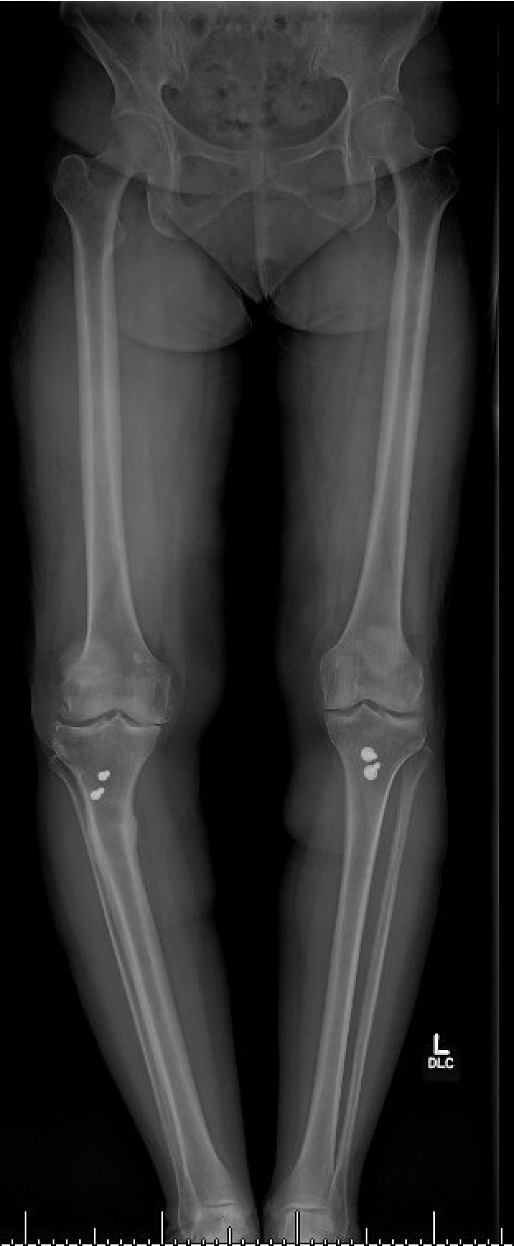

Pre-operative radiographs demonstrated Kellgren-Lawrence grade 4 tricompartmental osteoarthritis, 12° of tibial varus, a 22 mm deviation of the mechanical axis toward the medial side of the knee center, and an apex of angulation located 6 cm below the joint line (Figures 1 and 2). A follow-up computed tomography scan confirmed the absence of rotational malunion.